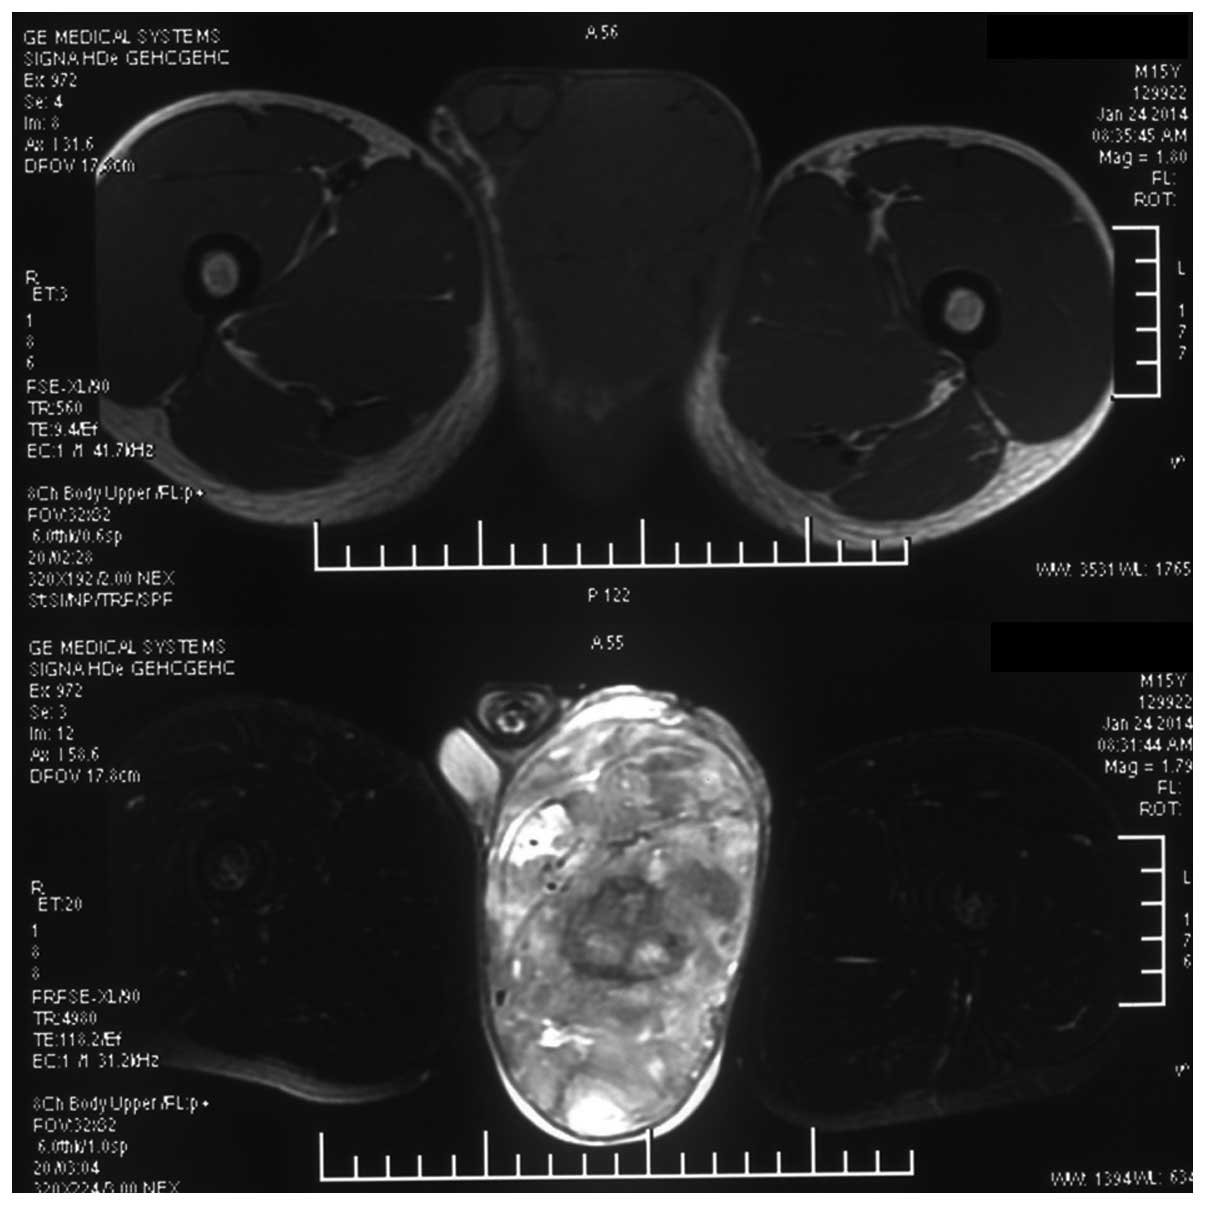

Rhabdomyosarcoma, MRI - Stock Image - C030/6339 - Science Photo Library

www.sciencephoto.com

www.sciencephoto.com

rhabdomyosarcoma mri

MRI Of Rhabdomyosarcoma And Other Soft-Tissue Sarcomas In Children

pubs.rsna.org

pubs.rsna.org

rhabdomyosarcoma mri embryonal sarcomas rg

MRI Of Rhabdomyosarcoma And Other Soft-Tissue Sarcomas In Children

pubs.rsna.org

pubs.rsna.org

rhabdomyosarcoma mri embryonal tissue sarcomas